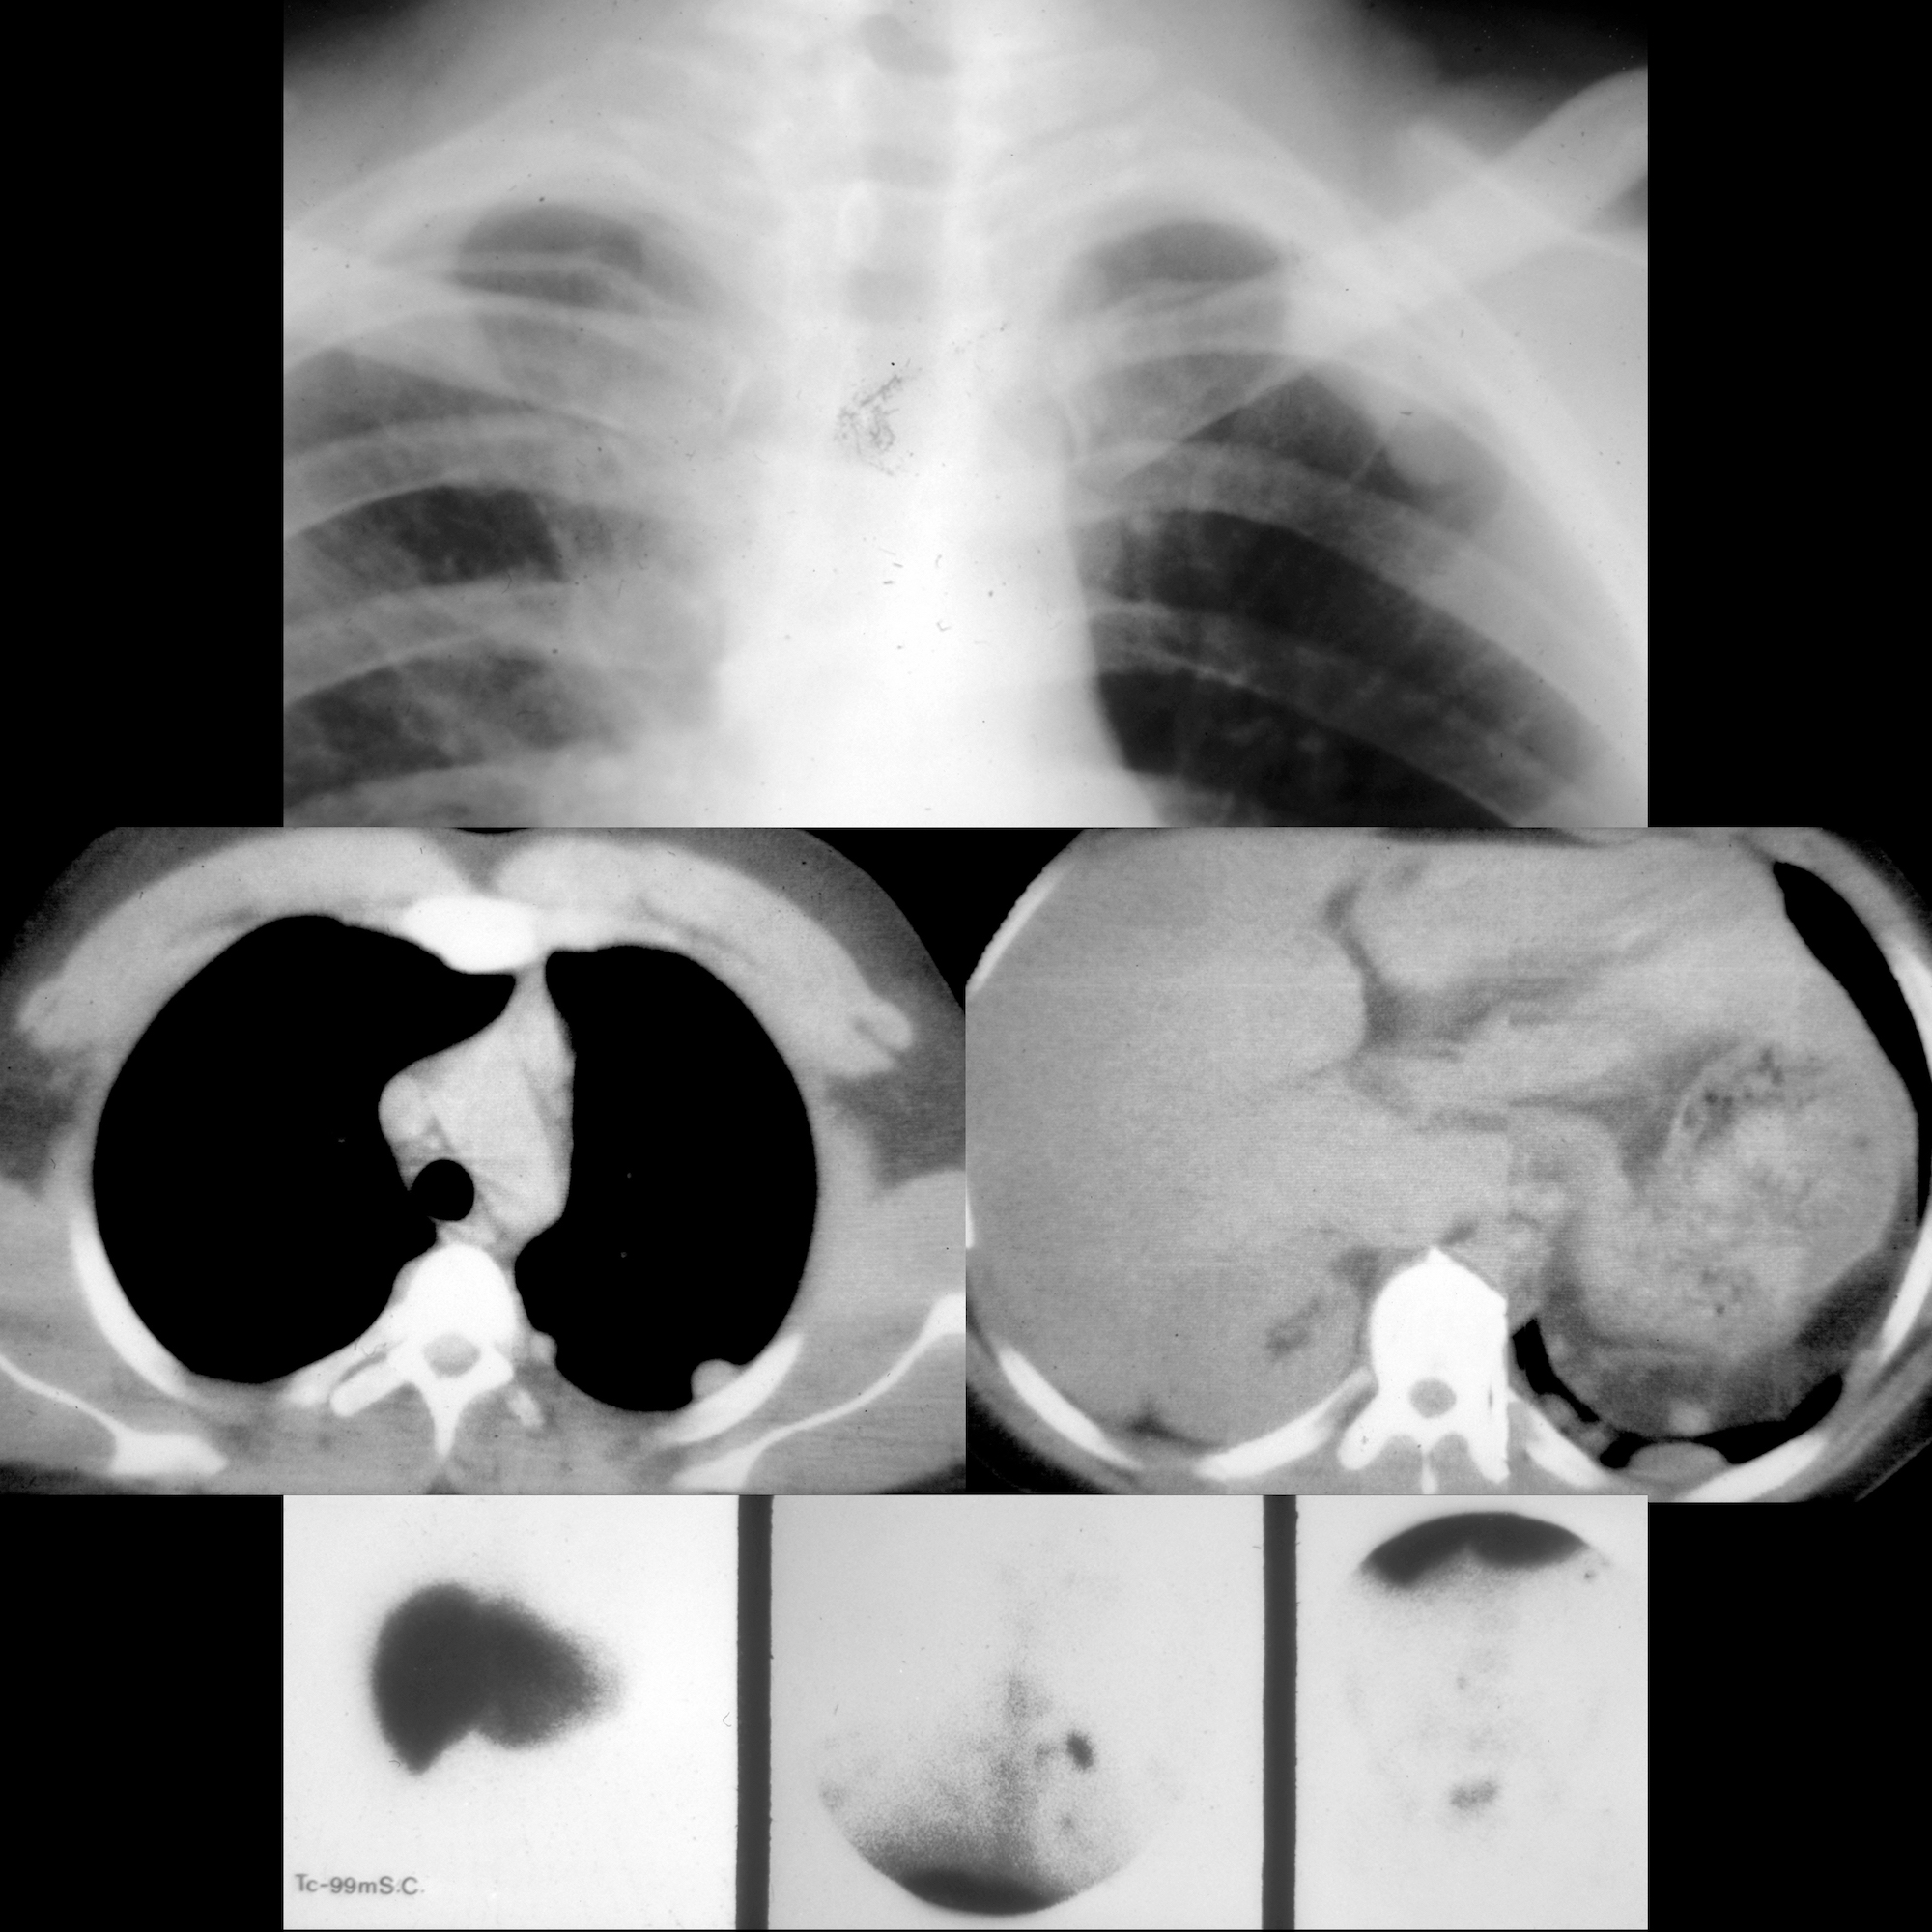

Traumatic diaphragmatic rupture Image

Radiology case Rupture of the diaphragm, diaphragmatic hernia Diaphragm Rupture Radiology Blunt trauma produces larger, radial. Specific diagnostic findings of diaphragmatic rupture on chest radiographs may not be seen in up to 50% of. Diaphragm and diaphragmatic injuries with kylee brooks md, parker hambright md, alexis holland md, and. Large defect in the left. Acute displaced fractures of the right anterolateral third through eighth ribs. Although the diagnosis may be obvious. Diaphragm Rupture Radiology.

Traumatic Diaphragmatic Rupture Radiology Key Diaphragm Rupture Radiology Although the diagnosis may be obvious at standard chest. Acute displaced fractures of the right anterolateral third through eighth ribs. Large defect in the left. Specific diagnostic findings of diaphragmatic rupture on chest radiographs may not be seen in up to 50% of. Blunt trauma produces larger, radial. Diaphragm and diaphragmatic injuries with kylee brooks md, parker hambright md, alexis. Diaphragm Rupture Radiology.